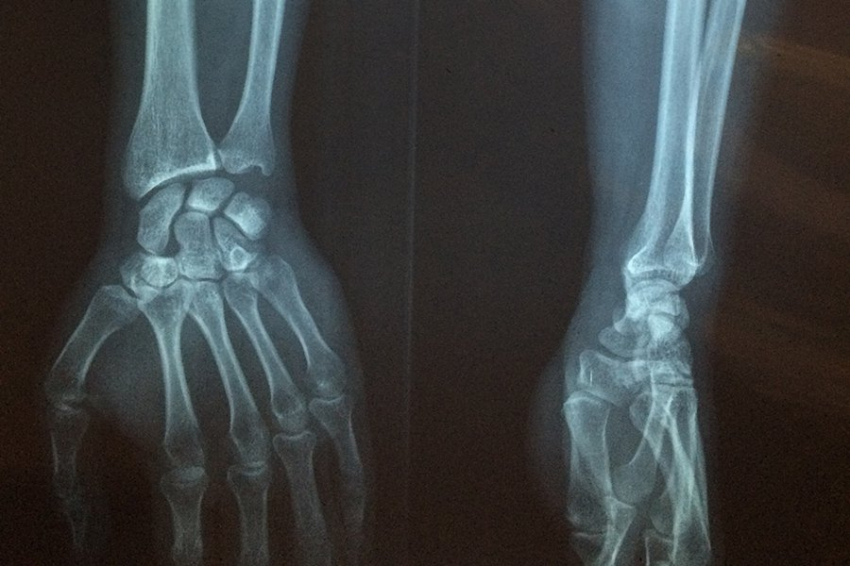

В современных скелетах крошечные кровеносные сосуды, которые проникают в твердый матрикс кости, обеспечивают проникновение клеток, называемых остеокластами, для разъедания старой кости и клеток, называемых остеобластами, для начала производства новой кости. Организацией процесса занимается третий набор клеток: остеоциты. Места восстановления, известные как остеоны, имеют характерные кольца, представляющие границы кровеносного сосуда и зоны существующей кости, разрушенной кости и новой кости. Процесс ремоделирования жизненно важен для восстановления и обновления кости, но у людей он может пойти не так, что приведет к остеопорозу, которым страдают более 10 миллионов человек только в Соединенных Штатах.